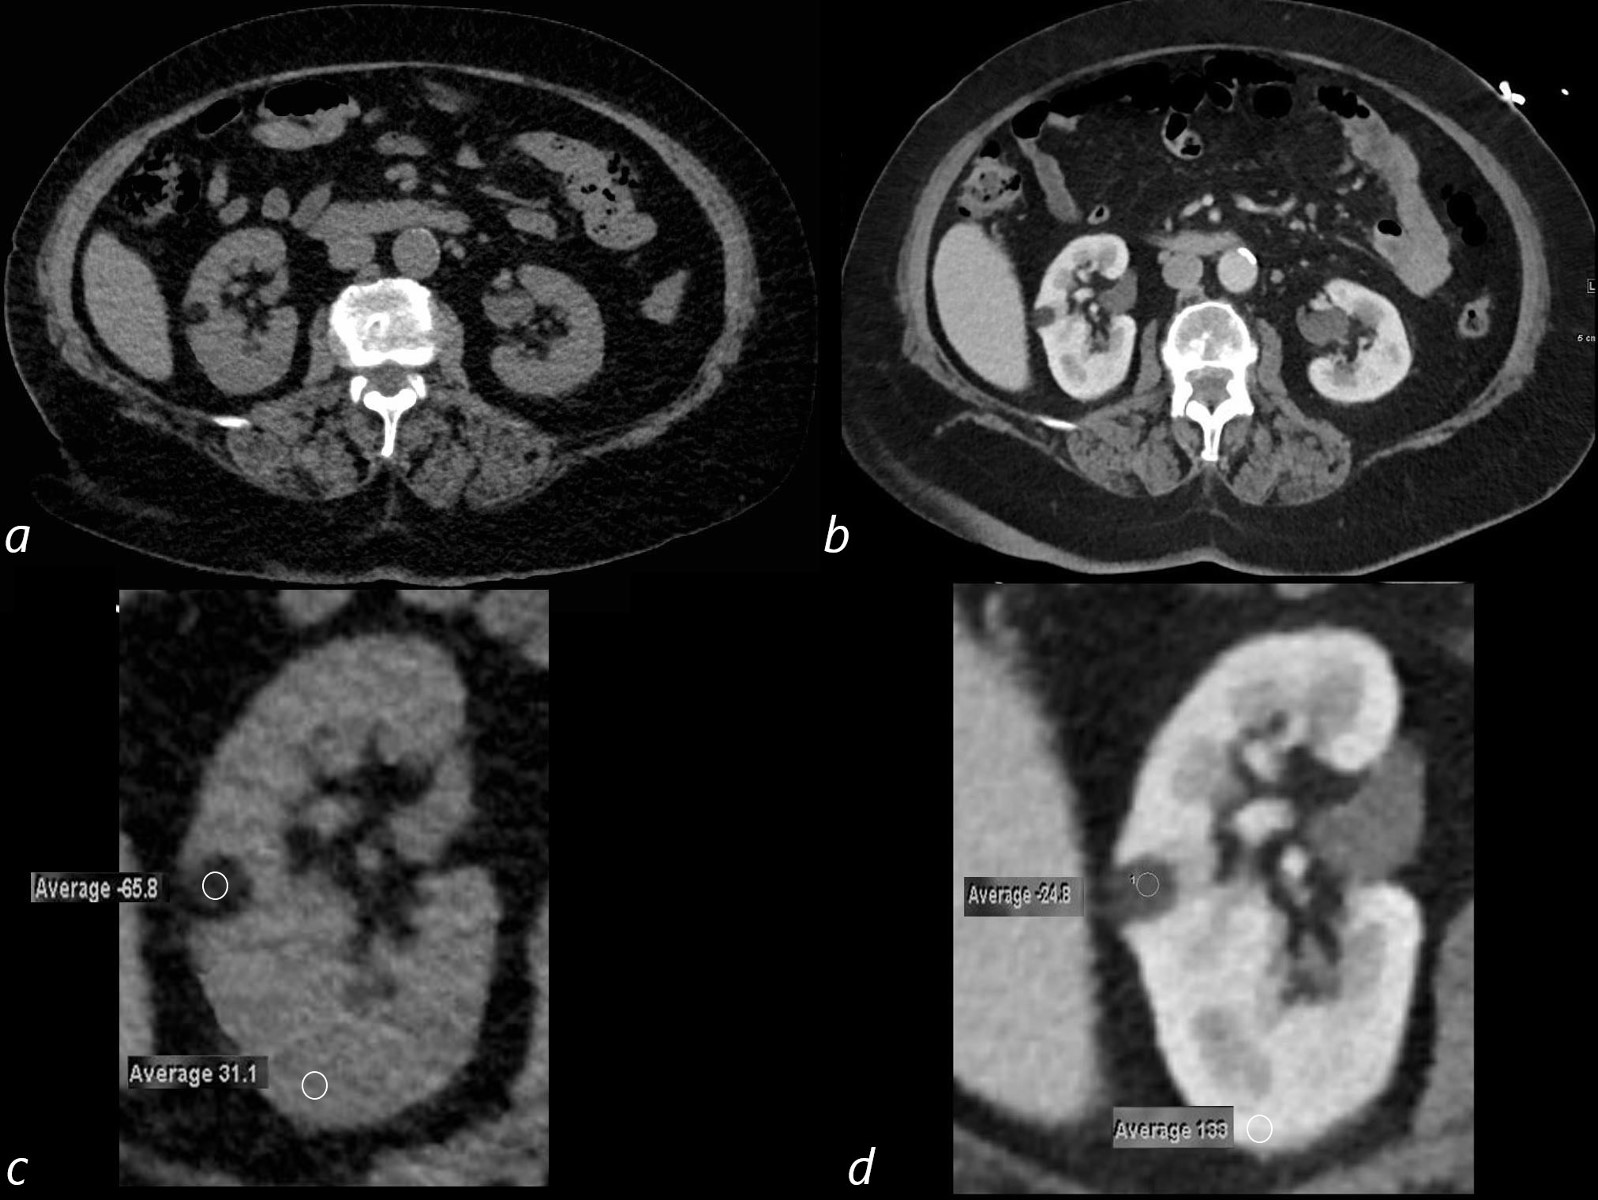

Learn about angiomyolipoma of the kidney, a common benign renal tumor. This guide covers essential information on symptoms, diagnostic imaging techniques, and effective treatment options, including embolization and surgery. Understand the risks associated with these growths and when clinical management is necessary for optimal renal health. Stay informed about managing this rare kidney condition with our expert overview.

Read full article: Angiomyolipoma Of The Kidney